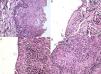

El estudio histopatológico de la muestra reveló una cavidad quística revestida por un epitelio poliestratificado paraqueratinizado con un estrato basal de células cilíndricas con núcleo hipercromático dispuesto en empalizada (fig. 2a). En función de estos hallazgos se diagnosticó la lesión como tumor odontogénico queratoquístico.

a) Microfotografía de biopsia inicial, se observa tejido constituido por una pared quística de tejido conjuntivo fibroso denso la cual conforma una cavidad virtual revestida por un epitelio plano poliestratificado. El estrato basal presenta células columnares de núcleo hipercromático con disposición en empalizada. La superficie epitelial se aprecia paraqueratinizada y corrugada. b), c) y d) Microfotografías de segunda biopsia. b) y c) Se aprecia membrana quística con epitelio de revestimiento plano pluriestratificado con pérdida de la estratificación celular, desorden de la capa basal, pleomorfismo celular, papilas en forma de gota y núcleos y nucleolos prominentes. La proliferación supera la membrana basal infiltrando el conjuntivo subyacente. d) Proliferación de células anaplásicas, plemórficas que crecen hacia la pared del quiste con zonas de invasión.